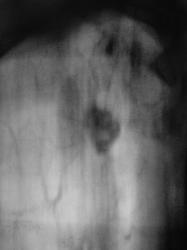

Контроль после флюорографии. Пациент давно снят с учета "у фтизиатра".

Пациент взят на "контроль" при расшифровке цифровых флюорограмм. Известно, что стоял на учете у фтизиатра. С учета снят 6 лет тому. Произведено стандартное рентгенологическое дообследование.

На 2 срезах очень похоже на туберкулому, и туберкулома не в спокойном состоянии.

Вполне спокойные туберкуломы.